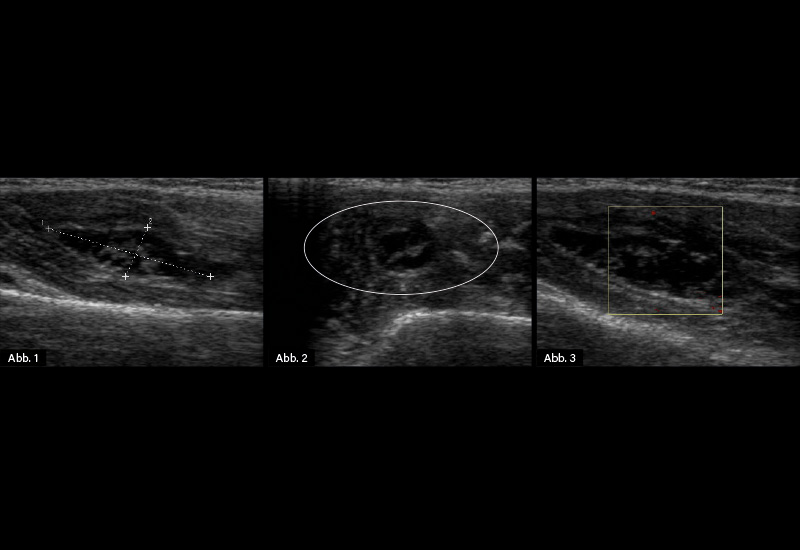

Bildgebende Diagnostik: Weichteilsonografie (s.u.)

Diagnose: Ganglion im Bereich des myotendinösen Übergangs des Musculus triceps brachii rechter Oberarm

Oberflächlich gelegene Ganglien können bereits klinisch identifiziert werden. Die Diagnosebestätigung und der Nachweis tiefer gelegener Ganglien erfolgt meistens sonografisch. Es kommt dann eine echofreie bzw. echoarme, gut abgrenzbare Struktur mit meist dorsaler Schallverstärkung zur Darstellung. In einzelnen Fällen kommt es bei chronischen Verläufen zur Eindickung der Ganglienflüssigkeit und echoreichen Binnenechos. Im Power-Doppler kann verständlicherweise kein Fluss nachgewiesen werden, dies dient auch der Unterscheidung zu vaskulären Strukturen. Bei ungünstiger Lage, die einer sonografischen Untersuchung nicht zugänglich ist, kann durch eine MRT-Untersuchung der Verdacht verifiziert werden.